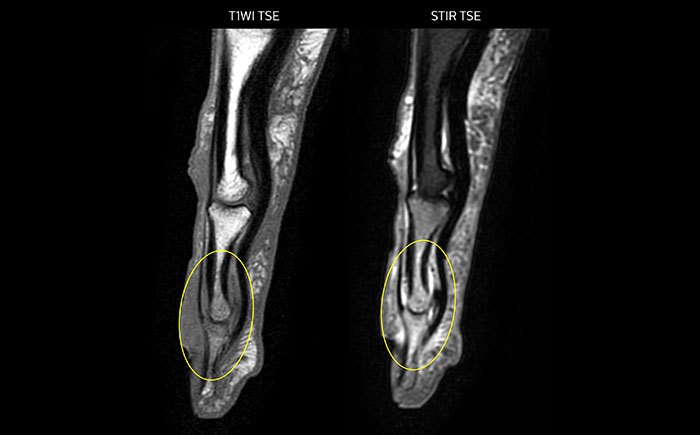

MRI examination on Prodiva 1.5T of a 72-year-old female with a malignant melanoma in the ankle. mDIXON TSE provides excellent fat suppression, without the distortion that is often seen at such extremities.

Scan time 2:55 min, FOV 160 mm, acq voxels 0.55 x 0.83 x 3.0 mm.

Scan time 4:19 min, FOV 160 mm, acq voxels 0.55 x 0.80 x 3.0 mm.

Scan time 2:50 min, FOV 160 mm, acq voxels 0.70 x 0.99 x 3.0 mm.